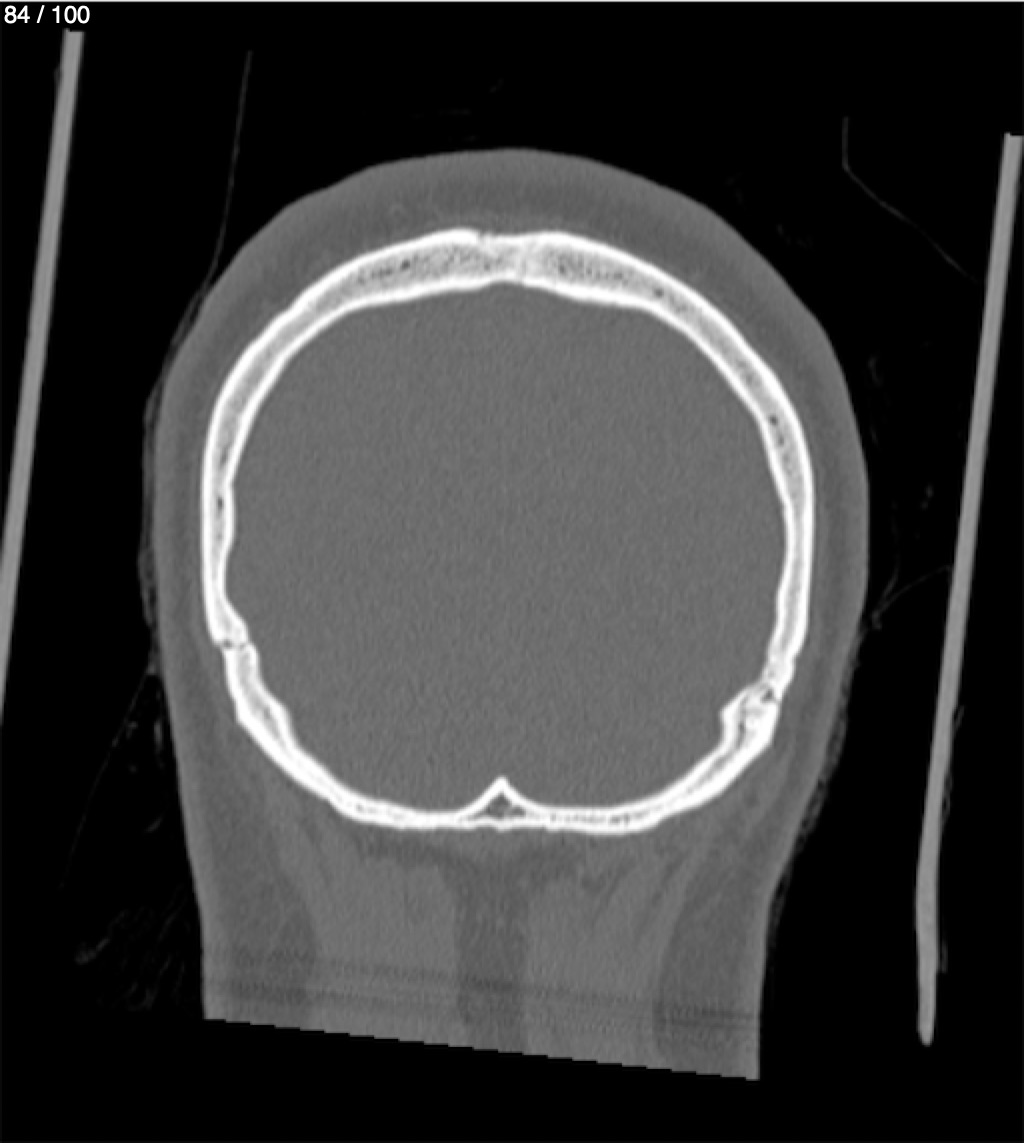

Reybet Garcia Fuentes 30A - T.C Craneo